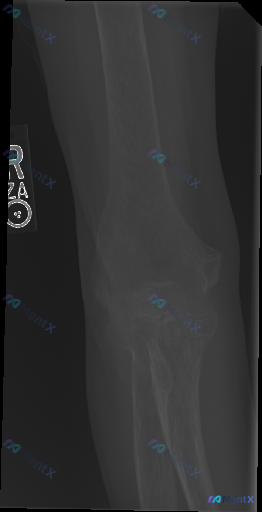

整理到一张右侧肘关节正位X光的读片讨论: 影像初步看下来: - 肱骨远端、尺桡骨近端骨质连续,关节对应关系尚可 - 关节间隙无明显狭窄/增宽,软组织也没看到明显弥漫肿胀 - 报告写的是「未见明显急性骨折或关节脱位征象」 但有意思的是,这份资料明确标注了「存在异常(Abnormality presen...